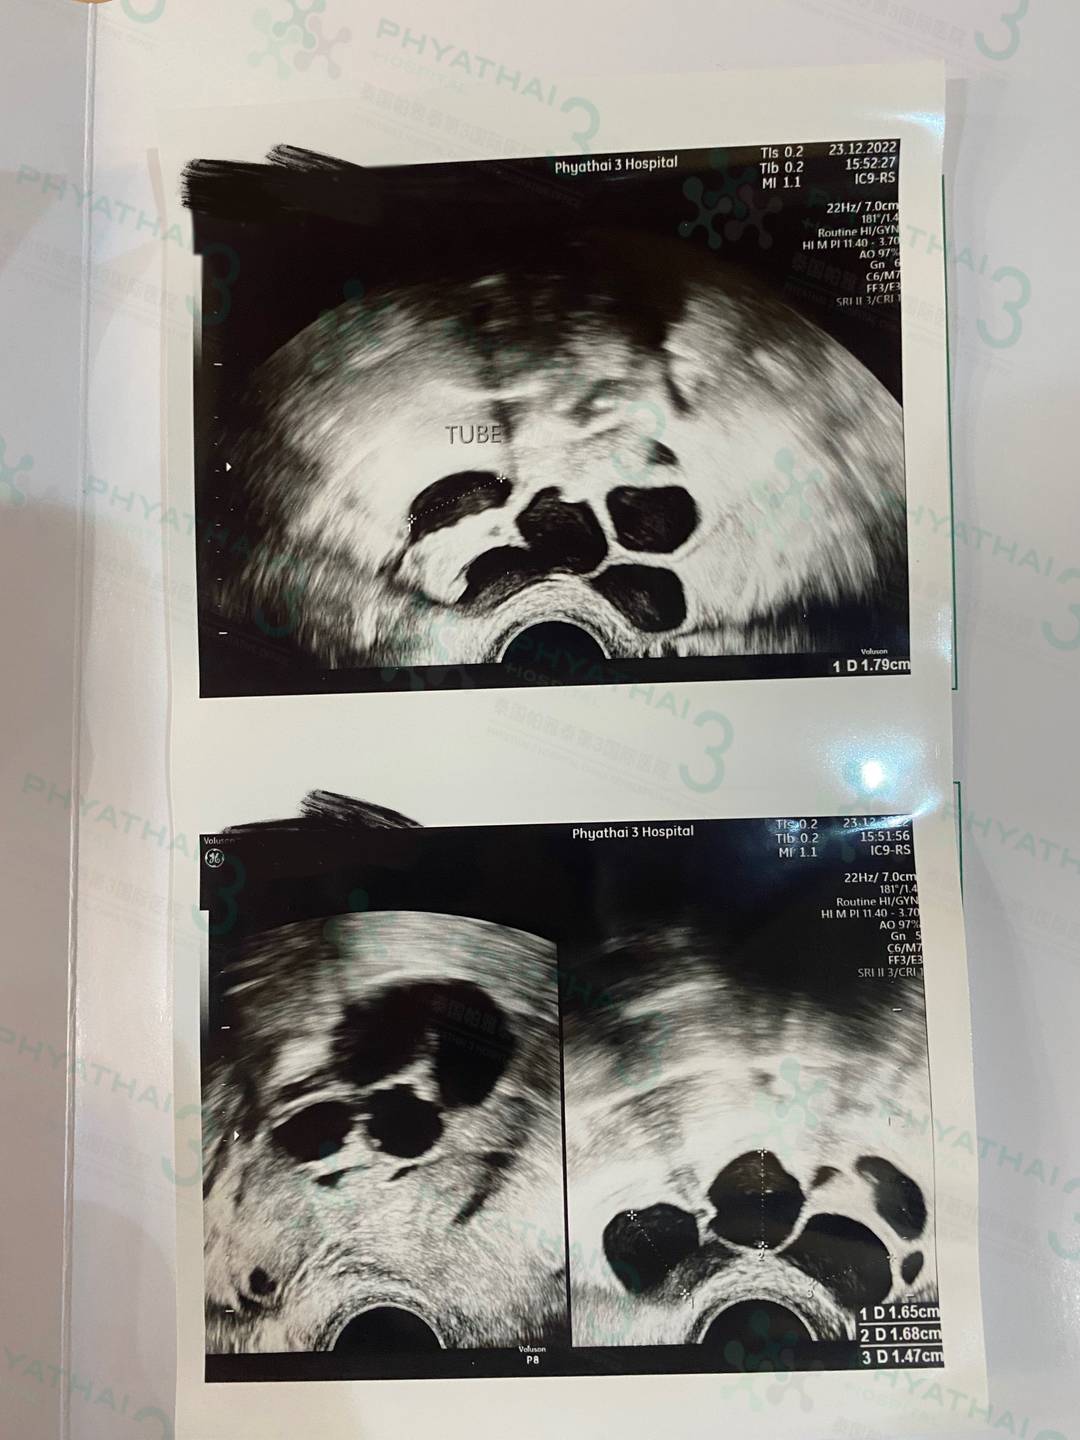

有卵泡但不确定会有卵子? 一般卵泡里面有卵子。卵泡从小卵泡逐渐发育生长,变成大卵泡,从小卵泡含有小卵子,卵泡在发育过程中,卵子逐渐生长、变大,卵泡成熟后,且受促卵泡素的刺激后,卵子才能成熟。每次见诊做阴超只能知道大概有几枚卵泡和大小,但是每个卵泡里面不确定会有卵子能用,所以取卵当天才能知道有几枚卵子可以做单精子注射